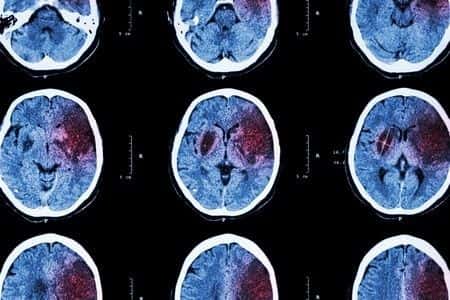

This case involves a 52-year-old woman with a history of high blood pressure who presented to an urgent care center with leg numbness. A CT was conducted and sent to an off-site radiologist for review. The radiologist reported acute cerebral infarction and suggested the patient receive an MRI to confirm. The urgent care center was closing for the evening and suggested the patient go home for the evening and come back to the urgent care center for the MRI the following morning. When she came back to the urgent care center, she received the MRI but was not seen by a doctor. The patient was discharged and told a doctor would follow up with her results in a few days. The next morning, the patient suffered a massive secondary stroke. The severity of the stroke caused permanent neurological damage to the patient. The MRI had shown a stroke in progress, which was never communicated to the patient. It was alleged that the urgent care facility should have transported the patient to a nearby hospital campus to be admitted under neurology as soon as the MRI was first recommended. An expert in emergency medicine was sought to review the facts of the case and opine on the standard of care.

I am a regional emergency department director in charge of 2 emergency departments and 2 urgent care centers. I manage physicians assistants, nurse practitioners, family practice physicians, and emergency medicine physicians. Approximately 60% of my time is clinical and I work clinically in the urgent care centers, in 2 inner-city community hospitals, and in a large academic center. Because of my position, I am directly responsible for quality and peer review committees. I am involved in quality and peer review committees for all the hospitals as well as system-wide, 14 hospital risk management. I see many cases involving stroke care and am familiar with the standard of care in the emergency department. I have reviewed many missed stroke cases. For a patient presenting with acute cerebral infarct, the standard of care is admission to the hospital within 48 hours due to increased risk of stroke. MRI of the brain with imaging of neck arteries (either CTA, MRA, or carotid doppler) should be completed upon admission. Cardiac echo should also be done as soon as possible. In a patient with acute infarct, referral/transport to a stroke center should be in an ambulance.